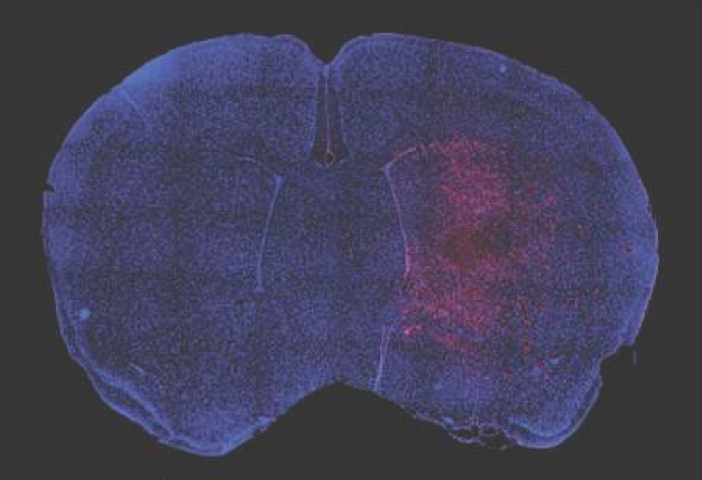

DECEMBER 5, 2017, New publication from the Aronin lab. Artificial miRNAs reduce human mutant Huntingtin throughout the striatum in a transgenic sheep model of Huntington's disease. Pfister E, Dinardo N, Mondo E, Borel F, Conroy F, Fraser C, Gernoux G, Han X, Hu D, Johnson E, Kennington L, Liu P, Reid S, Sapp E, Vodicka P, Kuchel T, Morton AJ, Howland D, Moser R, Sena-Esteves M, Gao G, Mueller C, DiFiglia M, Aronin N. Hum Gene Ther. 2017 Dec 5. doi: 10.1089/hum.2017.199.

DECEMBER 5, 2017, New publication from the Aronin lab. Artificial miRNAs reduce human mutant Huntingtin throughout the striatum in a transgenic sheep model of Huntington's disease. Pfister E, Dinardo N, Mondo E, Borel F, Conroy F, Fraser C, Gernoux G, Han X, Hu D, Johnson E, Kennington L, Liu P, Reid S, Sapp E, Vodicka P, Kuchel T, Morton AJ, Howland D, Moser R, Sena-Esteves M, Gao G, Mueller C, DiFiglia M, Aronin N. Hum Gene Ther. 2017 Dec 5. doi: 10.1089/hum.2017.199.